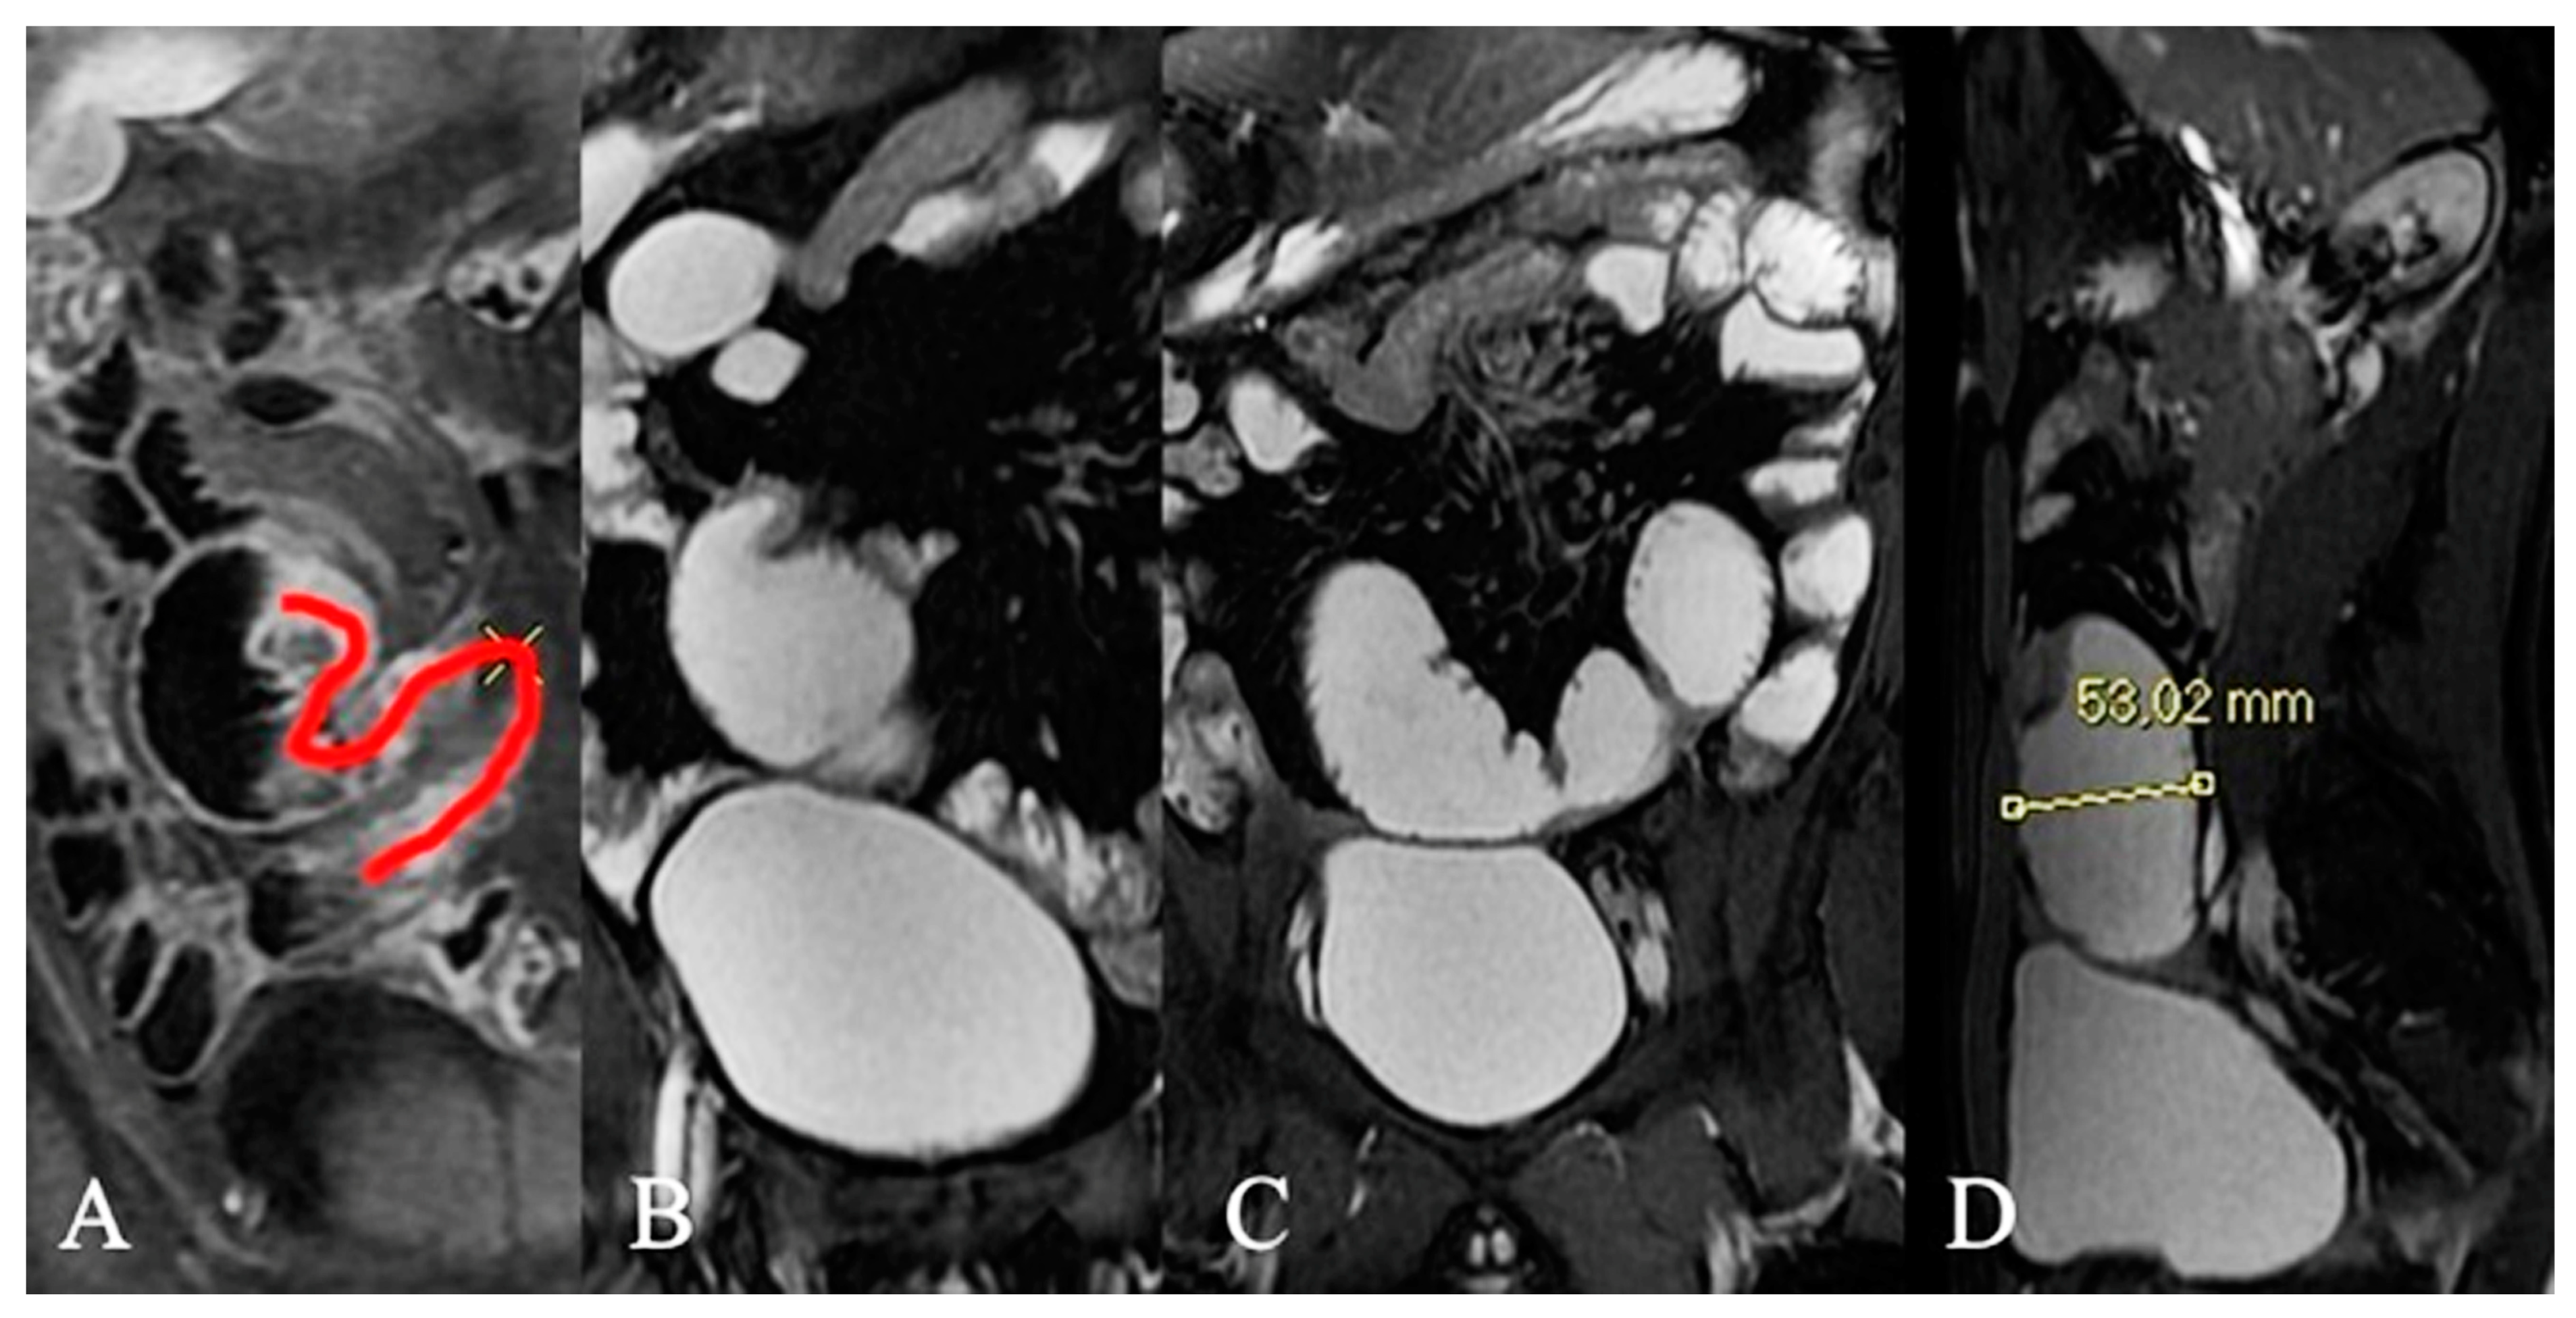

- Hu, J.; Yin, C.G.; Hu, K.F.; Li, G.W. The magnetic resonance enterography imaging features of symptomatic Meckel’s diverticulum in pediatric patients: A retrospective observational study of 31 cases. Transl. Pediatr. 2021, 10, 1974–1988. [Google Scholar] [CrossRef] [PubMed]

- Pierro, A.; Rotondi, F.; De Ninno, M.; Sallustio, G. Pseudodiverticular exophytic growth of a GIST of the jejunum with focus on imaging. Dig. Liver Dis. 2018, 50, 722. [Google Scholar] [CrossRef]

- Guglielmo, F.F.; Anupindi, S.A.; Fletcher, J.G.; Al-Hawary, M.M.; Dillman, J.R.; Grand, D.J.; Bruining, D.H.; Chatterji, M.; Darge, K.; Fidler, J.L.; et al. Small Bowel Crohn Disease at CT and MR Enterography: Imaging Atlas and Glossary of Terms. Radiographics 2020, 40, 354–375. [Google Scholar] [CrossRef]